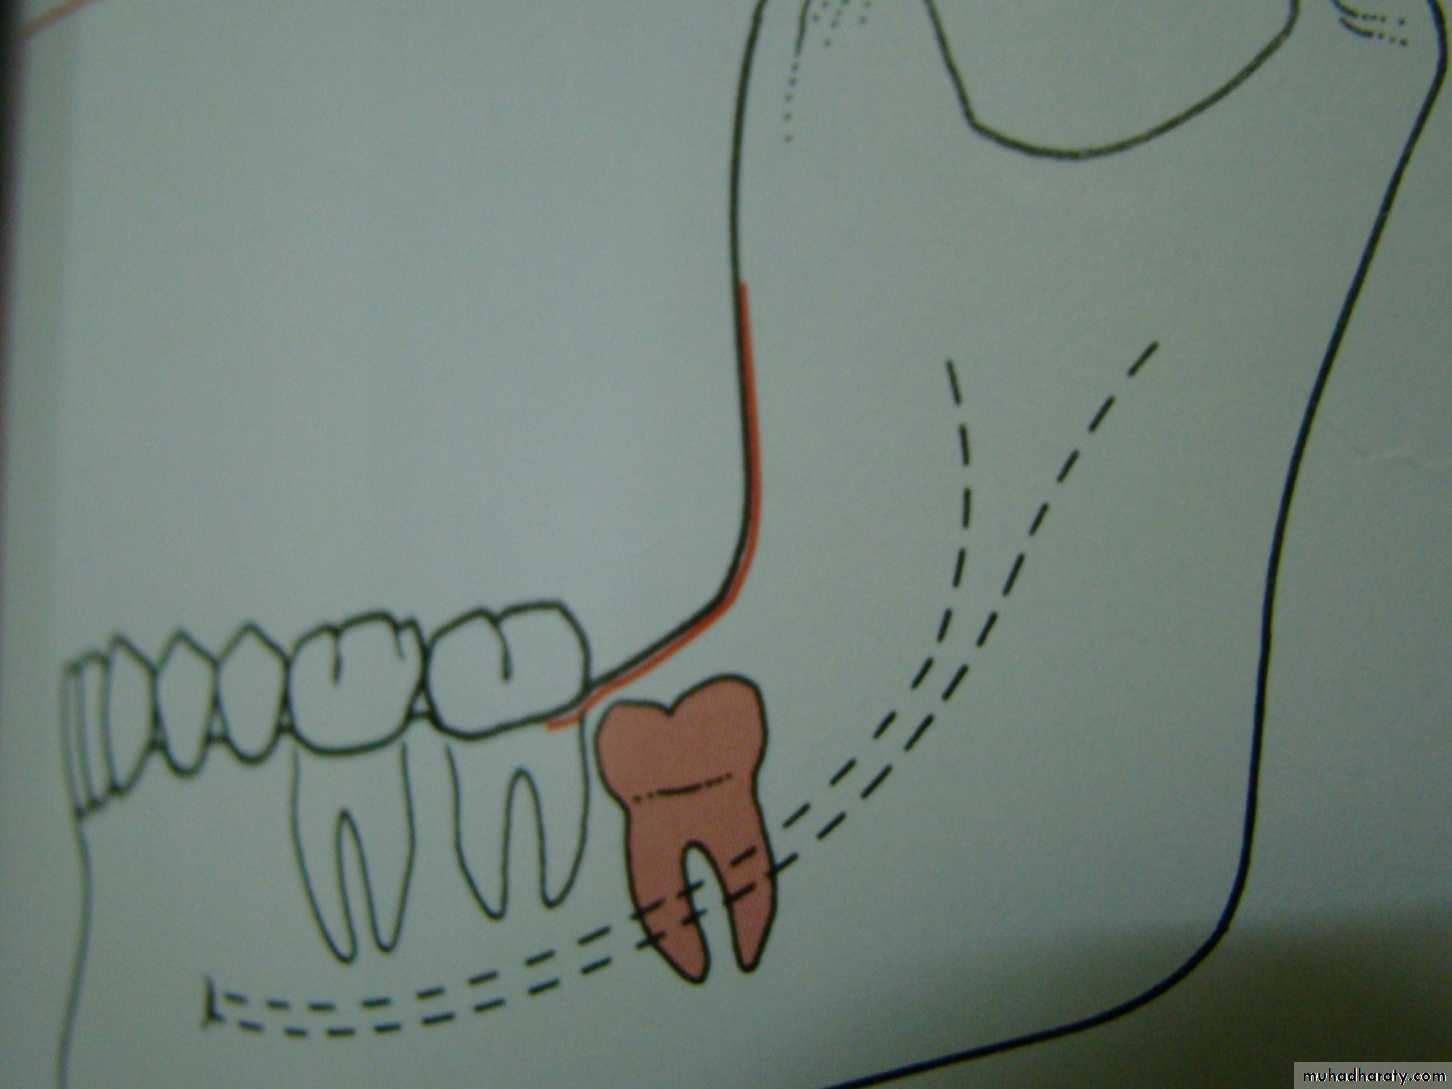

Winters classification of impacted lower third molar

mesioangular

hotizontalvertical

distoangular

Winter’s lines

1-White line: it is an imaginary line draw along the occlusal surface of erupted first and second molars extend posteriorly over 3rd molar region . Its benefit is to determine the angulations of an impacted tooth and its relationship with occlusal surface of erupted 2nd molar(depth).2- Amber line: It is a line drawn from the surface of bone laying distally to the 8 and to the crest of interdental septum or alveolar septum between 6 and 7. it determine the amount of bone removal

3-Red line : it is draw perpendicular from amber line to an imaginary point of elevator application located mesially to the CEJ except in Disto angular impaction it is distally located . It is used to measure the depth of the impacted tooth.

Note: Any tooth with red line length more than (5 mm) it is better to remove it under G.A.